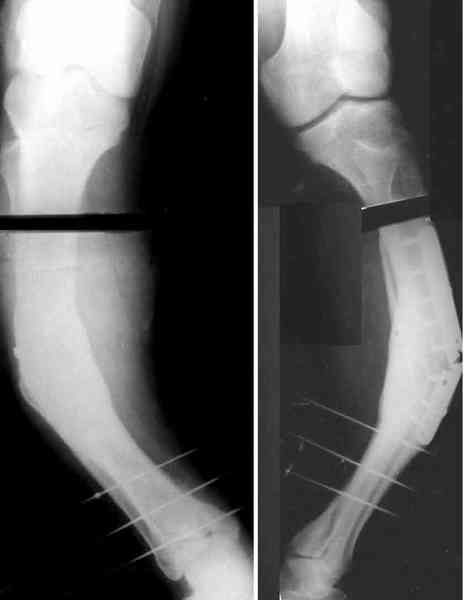

Глубокоуважаемые коллеги, Пациент 22 лет, 2,5 года назад оперирован у нас в институте по поводу низкого перелома бедра. Пару недель назад упал навзничь, поскользнувшись. Сломал бедро выше пластинки - снимок в приложении.Как бы вы поступили в данном случае?Если бы пластинку удалили сразу после сращения, интересно, предотвратило бы это подобный перелом? -- Best regards, Alexander N. Chelnokov

Удалили пластинку из двух доступов, винтик и спицу оставили. Сделан закрытый интрамедуллярный остеосинтез без рассверливания, прошло без

особенностей, стержень взял покороче, чтобы только до винта дошел. Снимок в приложении.

Кликните для загрузки файла 2k20309a.jpg

19KB (19793 bytes)

Для продолжения темы - несколько картинок.

Пациент 30 лет, лет пять назад оперирован по поводу перелома голени пластиной. Находясь на героине, нарушил режим, пошел, сломал и ногу и

пластину, но перелом сросся.

В приложении - внешний вид и рентген.

Пластинку и винты мне удалось разглядеть только на профильной проекции, точнее, трехчетвертной, судя по виду коленного сустава (правый снимок). На фасной - вообще не могу разобрать, где она :( Но, в конце концов, можно и не видя ее сказать, что уровень остеотомии может быть и другим, ниже или выше пластинки, придется только компенсировать смещение по ширине, которое появится при полном устранении угла не на вершине.